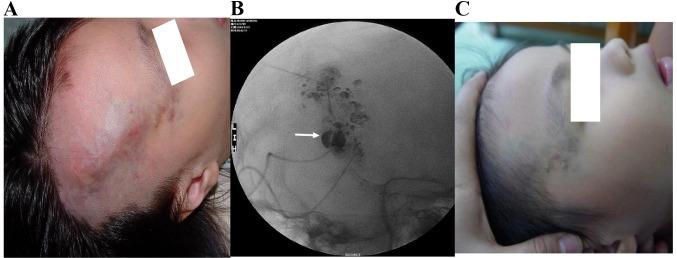

The aim of the present retrospective study was to investigate the clinical safety and efficacy of absolute ethanol combined with n-butyl cyanoacrylate sclerotherapy in the treatment of Puig's classified advanced venous malformation. Sclerotherapy was performed in 121 children (52 males and 69 females; age range, 5 months to 16 years) with venous malformations under general anesthesia between April 2009 and October 2014 at the Department of Interventional Radiology and Vascular Anomalies, Guangzhou Women and Children's Medical Center, Guangzhou, China. The patients with venous malformations were diagnosed and classified according to the diagnostic criteria of the International Society for the Study of Vascular Anomalies. According to the characteristics of intraoperative percutaneous angiography, 21 patient cases (9 males and 12 females; age range, 6 months to 14 years) were classified as advanced Puig's venous malformation. These 21 patients were treated with absolute ethanol combined with n-butyl cyanoacrylate. The patients were followed-up for 6-24 months (average, 15 months) after treatment. Following treatment with absolute ethanol combined with n-butyl cyanoacrylate, 15 cases were controlled and the total effective rate was 71% (15/21). However, 1 patient developed skin ulcerations, which was classed as a minor complication, 1 patient developed ectopic embolism caused by n-butyl cyanoacrylate reflux, and 1 patient developed transient pulmonary hypertension, the latter two complications were classified as major. Notably, the incidence rate of minor and major complications were 14.3%. To conclude, the present findings indicated that absolute ethanol combined with n-butyl cyanoacrylate sclerotherapy was a safe and effective method with a low complication rate in the treatment of Puig's classified advanced venous malformation in patients.